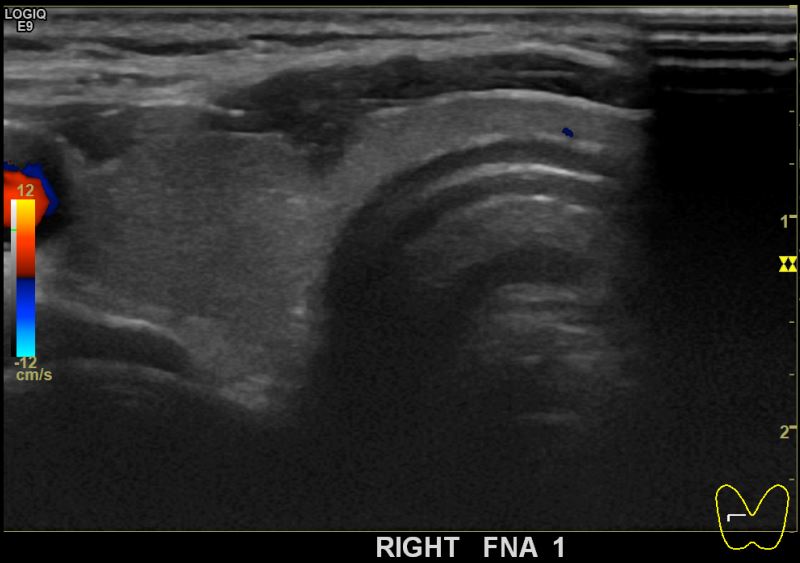

상기환자  40대 후반 여성분으로 의심스러운 우엽혹 세포검사진행후 갑상선암으로 진단되었습니다